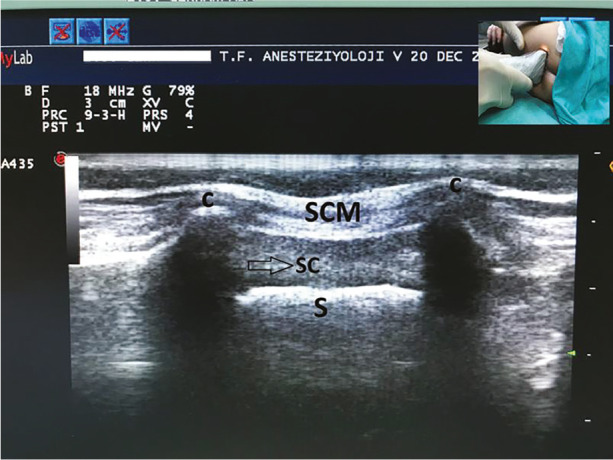

Methods: This study included 348 children aged 1 to 84 months, who were divided into three age groups: 1-24 months, 25-48 months, and 49-84 months. Sacral cornua were assessed using both palpation and ultrasound imaging. Palpation findings were categorized as "good", "difficult", or "non-palpable". Ultrasound imaging of the sacral cornua was classified as "clear", "unclear", or "invisible". Measurements taken included the inter-cornual distance, the anteroposterior diameter of the sacral canal, the distance from the skin to the sacral canal, and the distance from the dural sac to the cornua level.

Results: Palpation of the sacral cornua was rated as "good" in 75.9% of patients, "difficult" in 22.4%, and "non-palpable" in 1.7%. All patients with "good" cornua palpation were also classified as "clear" on ultrasound imaging. Among the cases with "difficult" palpation, 76% showed a "clear" ultrasound image, while 24% were "unclear". Only one patient had "invisible" cornua on ultrasound. The mean distance from the dural sac to the cornua level was 3.72±1.64 cm, and this distance increased significantly with age (P < 0.01).

Conclusion: Ultrasound is a valuable tool for identifying the sacral cornua, especially when palpation is difficult, and offers reliable, detailed information on sacral anatomy.